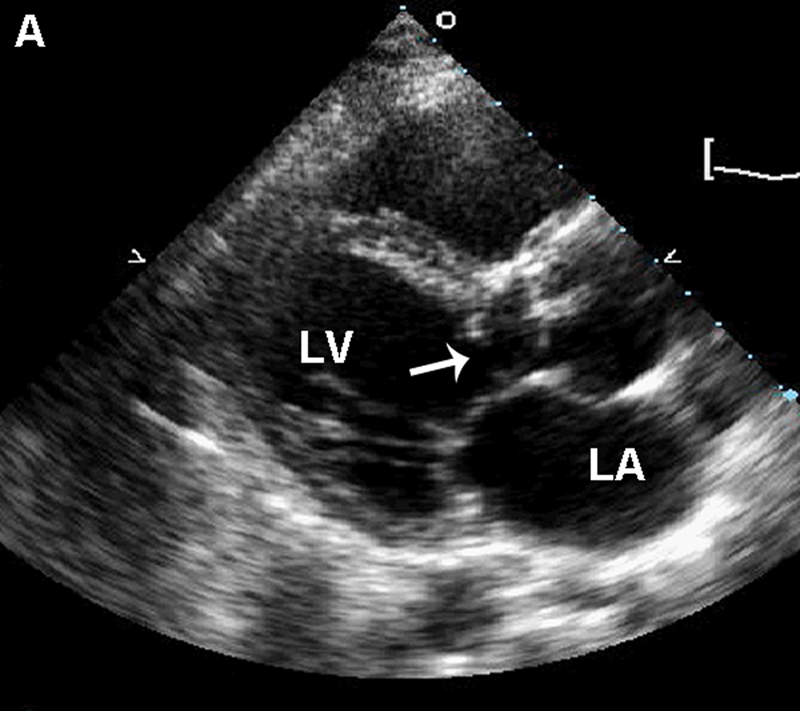

فحوصات تشخيصية لبعض امراض القلب والشرايين التاجية